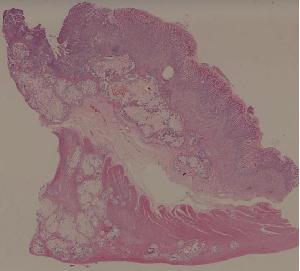

61.胃腺癌(胃粘液腺癌)